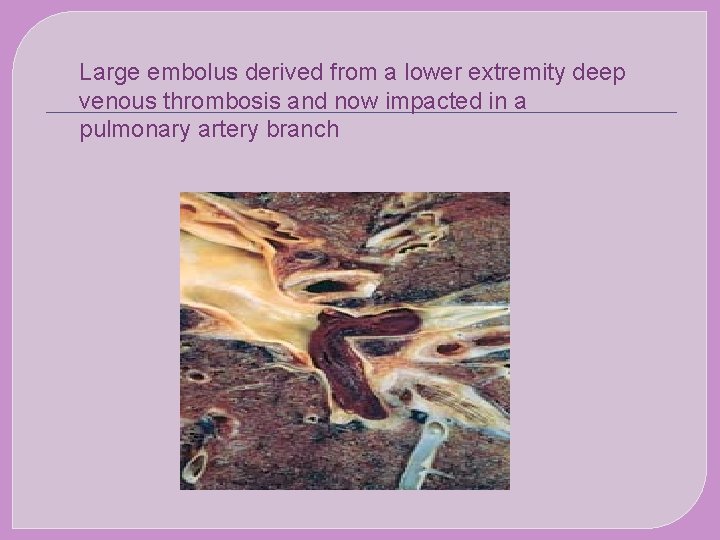

Large embolus derived from a lower extremity deep venous thrombosis and now impacted in a pulmonary artery branch